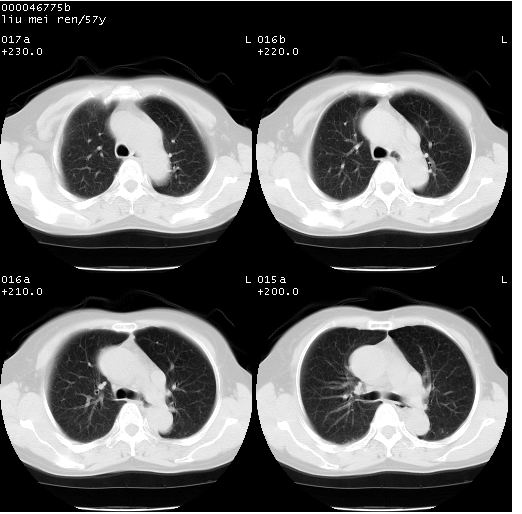

患者 女,57岁。因车祸受伤,其家属要求行“全身ct检查”。平素健康。

胸部ct轴位平扫(层厚10mm,螺距1.5,重建间隔10mm),图像如下:

左位上腔静脉,先天变异。

左位上腔静脉,先天变异。与双侧上腔静脉区别。